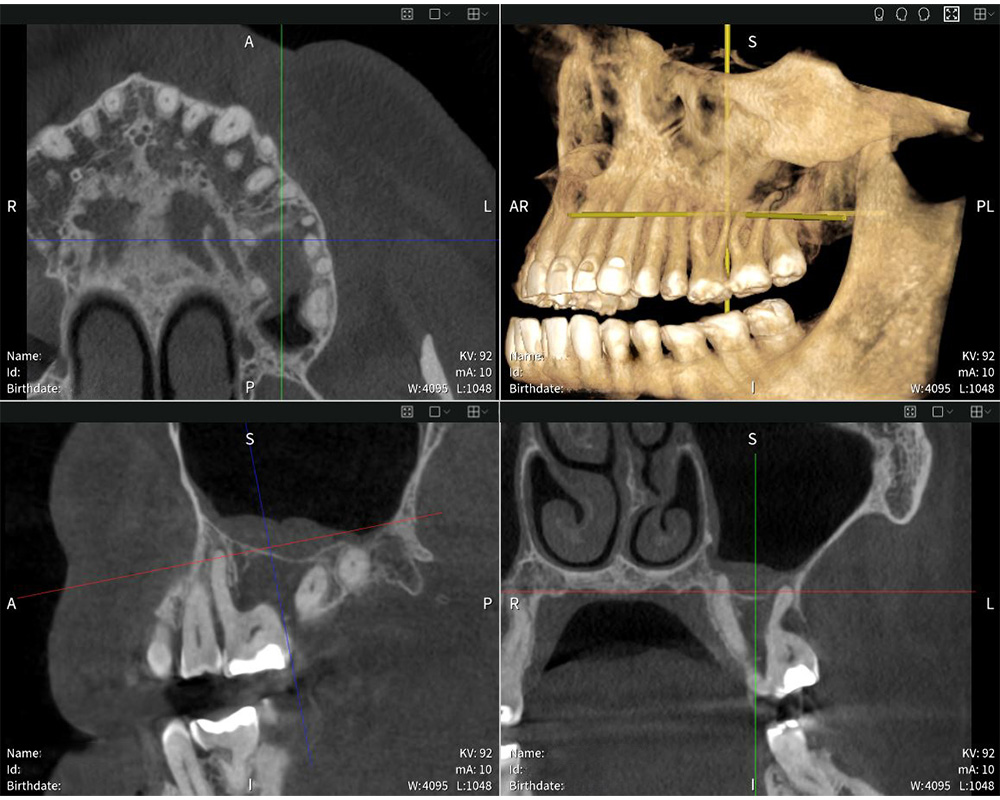

Seethrough Max puts usability first. Its open design and generous dimensions ensure maximum patient comfort and tolerance, while face-to-face positioning simplifies interaction between user and patient. “The positioning process is excellent. I appreciate being able to face the patient directly and maintain eye contact, which helps me guide them into the optimal position for a precise scan”, says Dr med. dent. Mauro Amato. Complementing the hardware, Seethrough Studio ensures sharp, detailed, and undistorted images. Its advanced patient motion correction algorithm enhances image quality in both 3D and 2D imaging. Offering a field of view of up to 17 × 17 cm, Seethrough Max covers a wide variety of applications, from endodontics and implantology to oral surgery and ENT – all while keeping radiation exposure low. “The X-ray images are exceptionally sharp and detailed, enabling highly accurate diagnoses and precise treatment planning”, says Dr med. dent. Mauro Amato.

Seethrough Flex is the compact model that matches the performance of its larger counterpart. It offers the best field of view to device dimension ratio on the market, with a FOV coverage up to 14 × 10 cm. Like Seethrough Max, the device benefits from the powerful Seethrough Studio Software, enhancing image quality and digital workflows. “I find the software very intuitive. The interface is user-friendly, and I can quickly access the tools and views I need”, explains Dr med. dent. Mauro Amato. He adds: “The software allows me to examine the images from every angle and find the answers I need efficiently”. Seethrough Studio is connected with ioDent® as standard. The advanced online platform from W&H combines important patient data, seamless communication and numerous useful services and support that make everyday practice life more efficient.